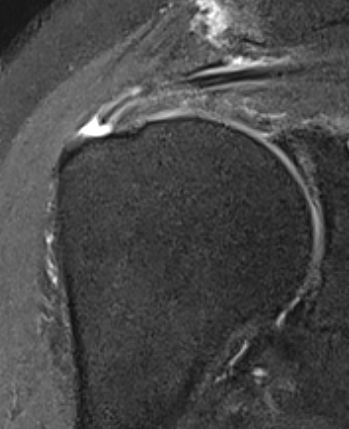

Articular Sided / PASTA (partial articular sided tendon avulsion)

Bursal Sided